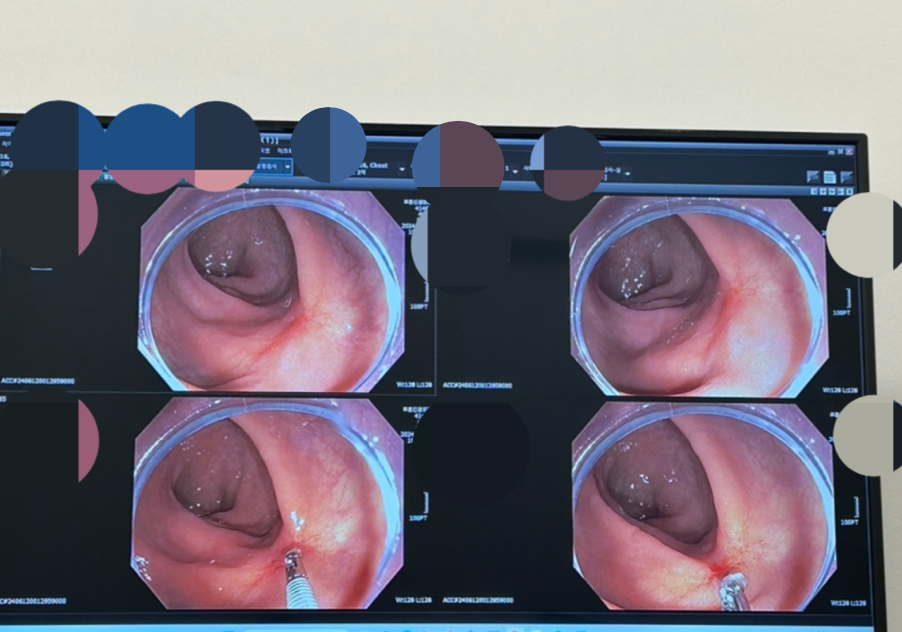

아래 사진은 그곳에서 조직을 떼어내는 장면이다.